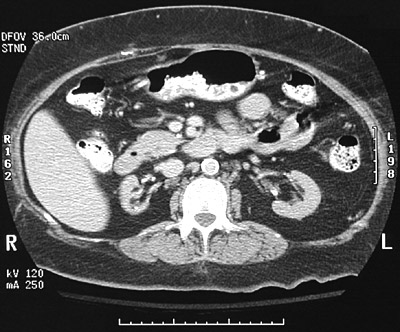

A 44-year-old man participates in a health screening program and is found to have a blood pressure of 166/106 mm Hg. He goes to a physician who finds no abnormalities on physical examination. Laboratory studies show sodium 140 mmol/L, potassium 3.9 mmol/L, chloride 104 mmol/L, CO2 25 mmol/L, glucose 93 mg/dL, creatinine 1.4 mg/dL and urea nitrogen 32 mg/dL. A urinalysis shows pH 6.5 with sp gr 1.018, and no blood, protein, glucose, or ketones. Urine electrolytes show sodium 15 meq/L and osmolality 600 mosm/L.

An abdominal ultrasound shows normal sized kidneys without dilation. The length between the markers is about 12 cm.